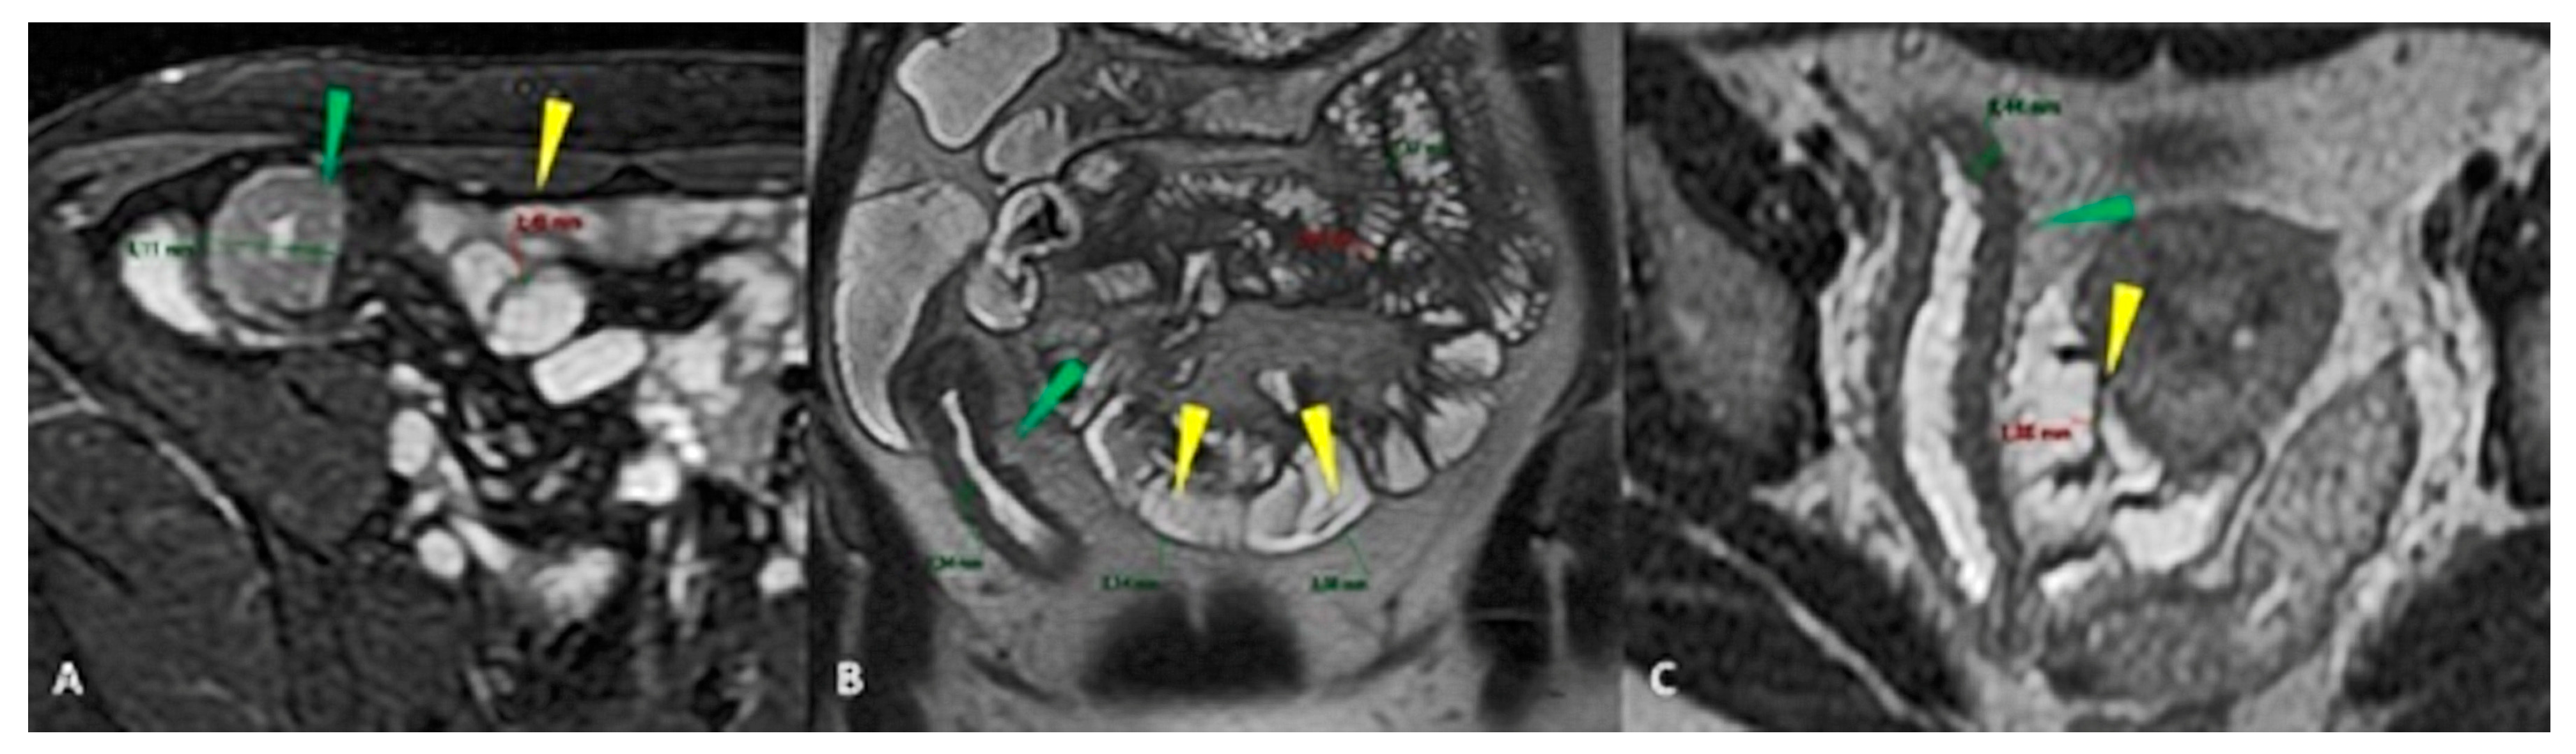

- Guglielmo, F.F.; Anupindi, S.A.; Fletcher, J.G.; Al-Hawary, M.M.; Dillman, J.R.; Grand, D.J.; Bruining, D.H.; Chatterji, M.; Darge, K.; Fidler, J.L.; et al. Small Bowel Crohn Disease at CT and MR Enterography: Imaging Atlas and Glossary of Terms. Radiographics 2020, 40, 354–375. [Google Scholar] [CrossRef]

- Marín-Díez, E.; Crespo Del Pozo, J. Diagnostic approach to small-bowel wall thickening: Beyond Crohn’s disease and cancer. Radiologia 2021, 63, 519–530. [Google Scholar] [CrossRef]

- Ahualli, J. The target sign: Bowel wall. Radiology 2005, 234, 549–550. [Google Scholar] [CrossRef] [PubMed]

- Walter, J.; Ayoob, A.; DiSantis, D. The bowel wall target sign. Abdom. Imaging 2015, 40, 457–458. [Google Scholar] [CrossRef] [PubMed]